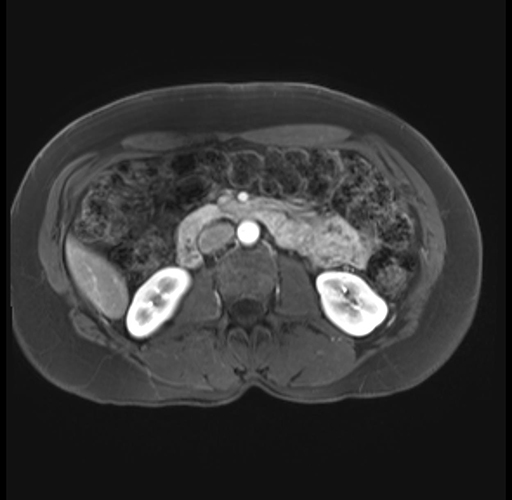

Imaging Analysis

Look through the patient's CT scan to identify any areas of concern for the necessary procedure.

Based on your CT findings, which issue(s) are present and would give reason for "planned slowing down moment(s)" in this case?